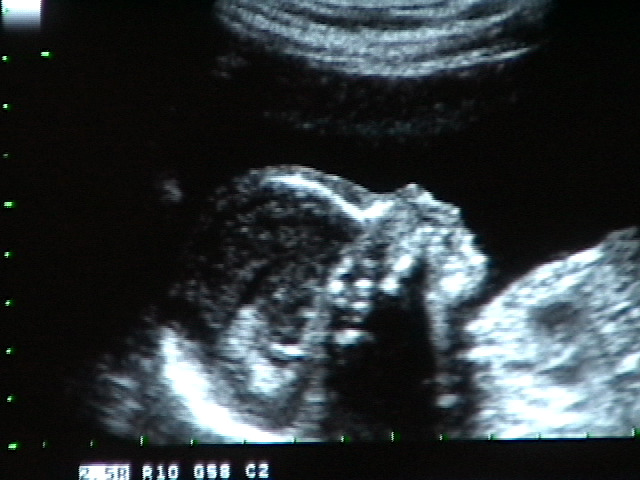

11. It’s a Girl!

• 2007-04-03

• Dave Allen Barker Jr

We got a sonogram today, and we have a girl on the way!

[Sonogram] “Hello?”

“I have a heart…” [Sonogram]

[Sonogram] “…and it beats!”